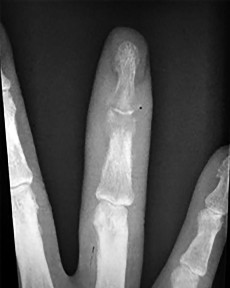

Question 19:

A 35-year-old volleyball player presents with the inability to actively extend the distal interphalangeal (DIP) joint of her long finger after a jamming injury. This classic mallet finger deformity represents a disruption of the terminal extensor tendon. If left untreated, what secondary digit deformity is most likely to develop over time?

Correct Answer: Swan neck deformity

Explanation:

A mallet finger results from the avulsion or rupture of the terminal extensor tendon at the base of the distal phalanx. If left untreated, the extensor mechanism retracts proximally, concentrating extensor forces at the central slip over the proximal interphalangeal (PIP) joint. This chronic imbalance leads to progressive hyperextension of the PIP joint combined with flexion of the DIP joint, clinically recognized as a swan neck deformity.